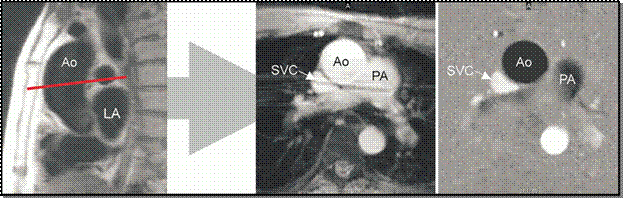

o Ascending Aorta- (a) Localizing (left), magnitude (middle), and velocity (right) images show a normal ascending aorta (Ao). The imaging plane is prescribed in an oblique sagittal localizing image (red line). LA = left atrium, PA = pulmonary artery. (b) Graph shows estimates of flow in the ascending aorta.